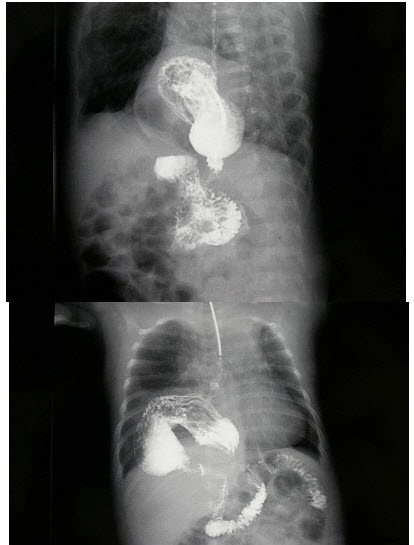

45、单项选择题

男,78岁,上腹痛1月余,返酸,无嗳气,空腹加重。体检:上腹压痛,结合图像,最可能的诊断为()

A.正常表现

B.慢性胃炎

C.胃癌

D.十二指肠憩室

E.十二指肠占位